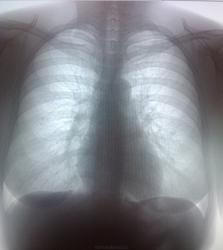

Сначала, в 11 году, был плотный очаг. К 2013 очевидно подрос, вполне может оказаться периферической опухолью.

На прямой р-грамме могут быть ретростернальные и парамаммарные регионарные л/у обеих молочных желез. Думаю: сначала в маммоцентр, потом КТ.

Если теоретически предположить, что плотная тень, видимая на прямой рентгенограмме - тень пара (ретро? интра?) маммарного (?) или ретростернального (?!!!) лимфоузла, патология которого обусловлена раком МЖ, возникает масса вопросов. 1. Почему столь жиденькая динамика метастаза (у молодой дамы!!!) за 2г? 2. Что все это время делает первичная опухоль? Ну, и в принципе: тень четко видна на боковом снимке, видно, что в легком. Нормальная современная тактика предложена во 2м посте. Но, конечно, обследовать МЖ никак не помешает)).

Создается впечатление, что тень не одна.Есть еще и справа и слева.

Петирфикат справа в S3 ( возможно в Sax )-если есть сомнения, возмите пациентку на R-скопию лёгких-определитесь с топографией изменённого участка ( имеет отношение к лёгочной ткани? какой сегмент ? и др.)

Периферический растет...

Девушка молодая,обидно пропустить патологию.Без сомнений,нечего гадать,надо делать РКТ.

Прямая и боковая разнятся (на мой взгляд) за счет суммации изображений обоих легких на боковой рентгенограмме. При всем уважении к линейной ТГ - в конкретном случае (молодая женщина, визуальный рост "очага", относительно малые его размеры, три года наблюдения, доверие клиницистов к КТ) сразу постарался бы найти возможность для КТ.

Обработанные снимки.